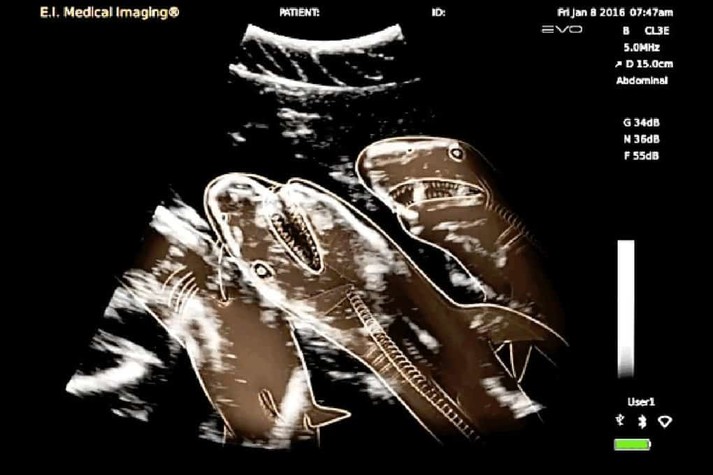

15 удивительных рентгеновских снимков беременных животных

Для женщины первое УЗИ запоминается на всю жизнь, но и рентгеновские снимки животных не менее удивительны

Но а как же выглядит беременность у братьев наших меньших?

Специалисты, которые по долгу своей работы наблюдают животных, готовых принести потомство, поделились этими удивительными рентгеновскими и ультразвуковыми снимками.